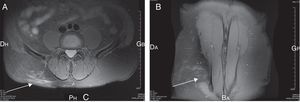

A 67-year-old male patient presented with acute thoraco lumbar and right trochanteric pain at the consultation of Rheumatology. The patient could not sleep due to the pain, mostly localized in the right iliac crest but irradiating to the trochanter. Pain was aggravated by pressure, right side-lying and seating postures. Magnetic resonance imaging of the spine revealed a lumbar myositis, with T2 high signals in the paraspinal muscles (L3–L4 area) (Fig. 1). There was no cutaneous eruption, no neck stiffness, no biologic inflammatory syndrome, no biologic sign of muscular lysis and no hypereosinophilia. Results of immunological investigations including complement fractions explorations, rheumatoid factor dosage and cryoglobulins detection, were negative. Results of serum antibody tests for Borrelia burgdorferi, Coxiella burnetti and Treponema pallidum were also negative. In contrast, the Toxocara canis serologic tests were strongly positive by both Toxocara enzyme-linked Immunosorbent assay and Toxocara Western blot assays. The patient did not have a dog but was living in a rural area and reported frequent contacts with soil. Pains disappeared rapidly after 4 days of albendazole treatment. Six months later, the patients relapsed with similar symptoms in intensity and location; the pains disappeared again after 4 days of albendazole treatment.